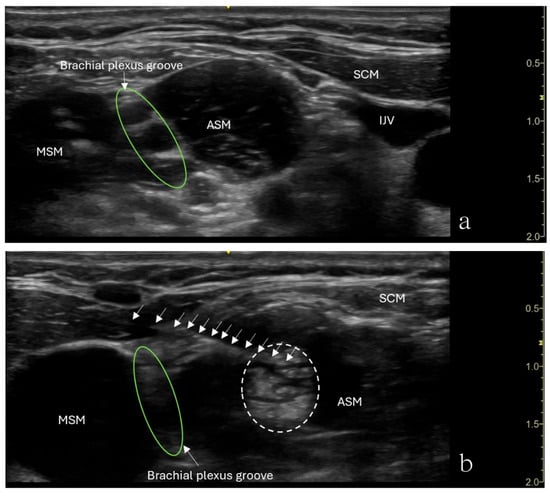

The patient underwent an ultrasound-guided right anterior scalene muscle block under minimal sedation. A high-frequency linear probe was used to identify the anterior scalene muscle (Figure 1). After sterile preparation, a 22-gauge, 50 mm Sono-TAP needle (PAJUNK®, Geisingen, Baden-Württemberg, Germany), using an in-plane technique, was advanced from the posterior aspect of the neck anteriorly and was inserted into the middle of the anterior scalene muscle. After negative aspiration of blood, 5 mL of 0.5% ropivacaine was slowly injected in increments. An increased muscle size was observed with no medication extravasation to the brachial plexus divisions (Figure 1). After the procedure, the patient’s preexisting numbness disappeared, her weakness in her right shoulder disappeared, and her hand strength improved. However, she reported shoulder heaviness though she had a full range of motion.

Figure 1.

Ultrasound image showing an anterior scalene muscle block in a 12-year-old girl. (a) SCM—sternocleidomastoid muscle, MSM—middle scalene muscle, ASM—anterior scalene muscle, IJV—internal jugular vein. The interscalene nerve roots (C5,6,7) are highlighted with a green circle. (b) The needle (arrows) is inserted into the middle of the anterior scalene muscle (ASM) from the posterior aspect of the neck anteriorly, with local anesthetic spreading within the muscle (dashed line). The brachial plexus groove lies between the ASM and MSM.